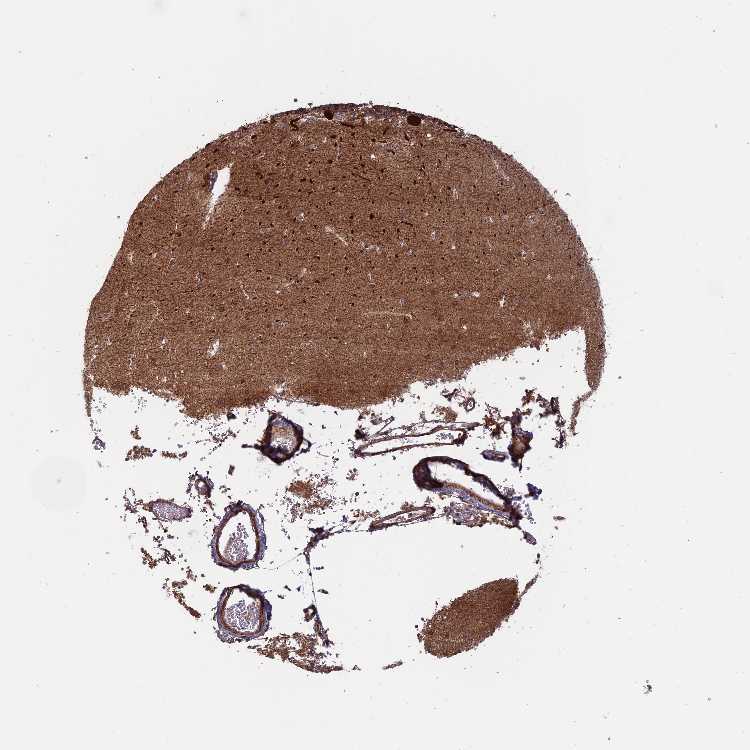

CEREBELLUM - Antibody stainingi

Antibody staining in the annotated cell types in the current human tissue is reported as not detected, low, medium, or high, based on conventional immunohistochemistry profiling in selected tissues. This score is based on the combination of the staining intensity and fraction of stained cells.

Each image is clickable and will lead to virtual microscopy that enables deeper exploration of all samples and also displays staining intensity scores, fraction scores and subcellular localization as well as patient and tissue information for each sample.

Antibody HPA039324

Purkinje cells High

Cells in granular layer Not detected

Cells in molecular layer Low